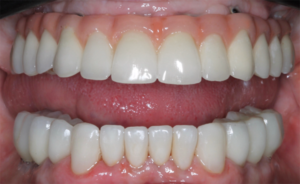

Figura 7 – Aspecto final da reabilitação dos arcos superior e inferior em cerâmica. Próteses confeccionadas pela Dra. Joraci Teixeira.